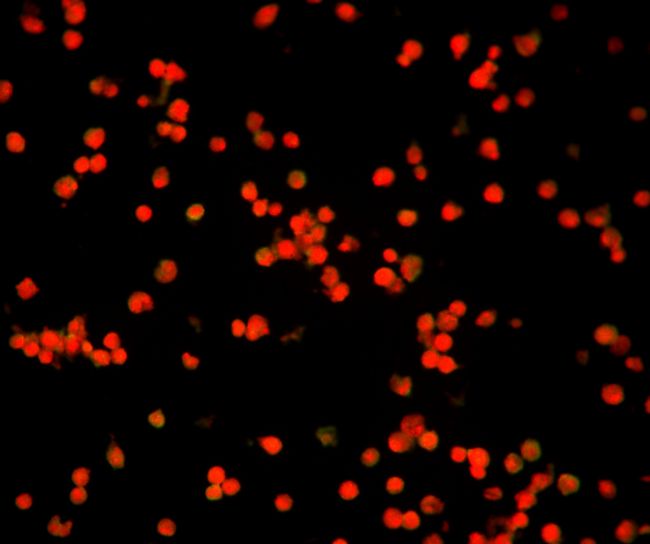

使用熒光

顯微鏡400倍視野觀察(40X物鏡),甲型流感檢測孔位熒光少且弱,視為陰性結果,熒光亮度強數量多,平均每個視野的陽性細胞大于3-5個,就可以判斷為陽性。乙型流感另有一個孔位,判斷標準和甲型流感一致。

流感病毒檢測陽性

MF31拍攝的流感病毒免疫熒光檢測